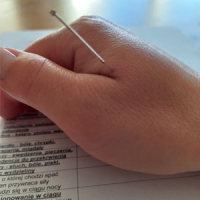

Paulina Praszkowska Położna, Akupunkturzystka i Moksoterapeutka

Pierwsza Wizyta Akupunkturowa

Wizyta akupunkturowa